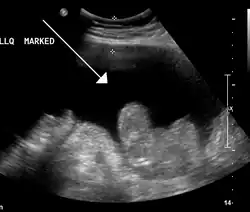

| Diagnostic method | Physical exam, ultrasound, CT scan[3] |

In the developed world, the most common cause is liver cirrhosis, whose underlying mechanism involves high blood pressure in the portal system and dysfunction of blood vessels. Other causes include cancer, heart failure, tuberculosis, pancreatitis, and blockage of the hepatic vein.[4] Diagnosis is typically based on an examination together with ultrasound or a CT scan. Testing the fluid can help in determining the underlying cause.[3]

Ultrasound investigation is often done before attempts to remove fluid from the abdomen. This may reveal the size and shape of the abdominal organs, and Doppler studies may show the direction of flow in the portal vein, as well as detecting Budd–Chiari syndrome (thrombosis of the hepatic vein) and portal vein thrombosis. The sonographer also can estimate the amount of ascitic fluid, and difficult-to-drain ascites may be drained under ultrasound guidance. An abdominal CT scan is more accurate than a sonogram to reveal abdominal organ structure and morphology.[13]